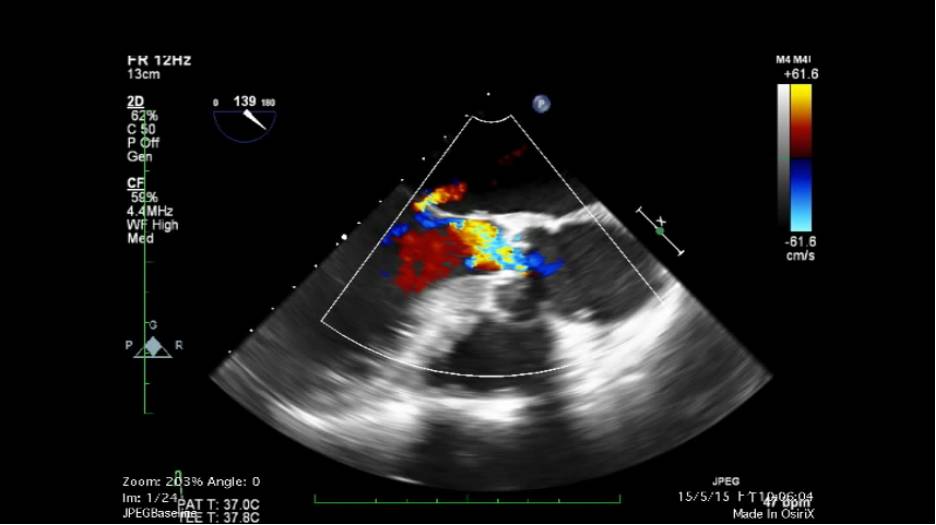

瓣膜反流(Regurgitation):血流逆流入上一级腔室,导致心脏腔室前负荷增加

瓣膜病变后单向阀门作用的散失,导致以肺淤血和腔静脉淤血为症候群的心力衰竭的发生。